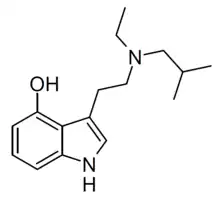

| EiPT | artificial | H | CH2CH3 | CH(CH3)2 | N-Ethyl-N-isopropyltryptamine | 848130-11-0 |